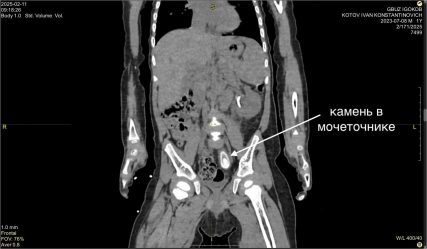

Камень в 3 см удалили из мочеточника маленького жителя Усть-Кута

Сложную операцию провел знаменитый на весь мир иркутский хирург, главный врач Иркутской областной детской клинической больницы Юрий Козлов. Первые признаки заболевания жительница Усть-Кута обнаружила у сына Вани еще в декабре прошлого года. На обследовании в Иркутске поставили диагноз — большой камень в нижней трети левого мочеточника размером около 3 на 1,5 см и вызванный им блок почки. Размер камня удивил медиков — это нетипично для таких маленьких пациентов. — Попытка внутрипросветного лечения была безуспешна — устье мочеточника не пропускало даже самую маленькую оптическую систему цистоскопа. После месяца непростого лечения с использованием нескольких антибиотиков была выполнена операция с применением нашего излюбленного подхода без разрезов — лапароскопии, — рассказывает Юрий Козлов. Операция прошла успешно, и сегодня Ваня чувствует себя прекрасно. Администрация УКМО